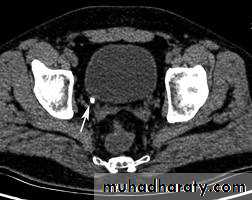

34- vesico-uretric junction stone (CT scan)